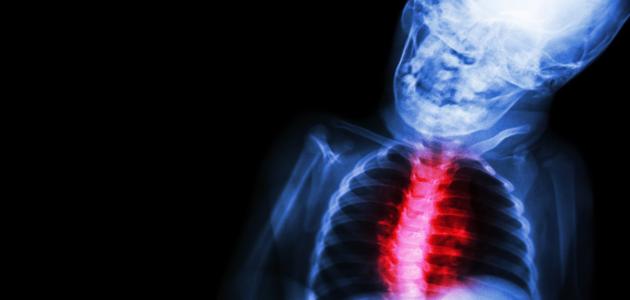

ما هو روماتيزم القلب

عمون - روماتيزم القلب هو مرض التهابي يؤثر على الأنسجة المحيطة بالقلب، وينتج عنه تلف وتضرر في صمامات القلب. يعتبر الروماتيزم القلب أحد أنواع التهاب المفاصل التأتبي الناتج عن عدوى بكتيرية بالبكتيريا المعروفة باسم العقديات البنيقة مجموعة أ (Streptococcus pyogenes).